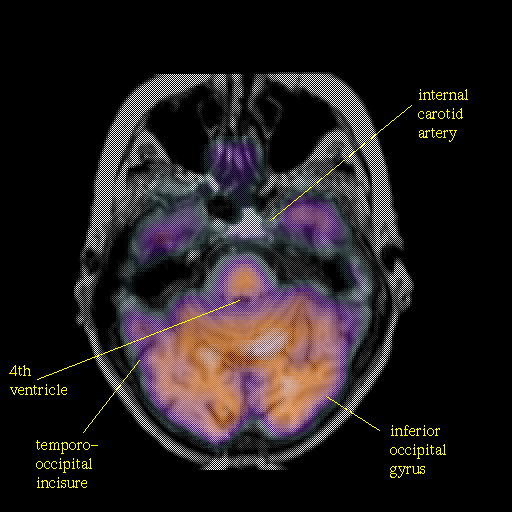

overlay: Slice 16

Slice 16

Pointers

Labeled